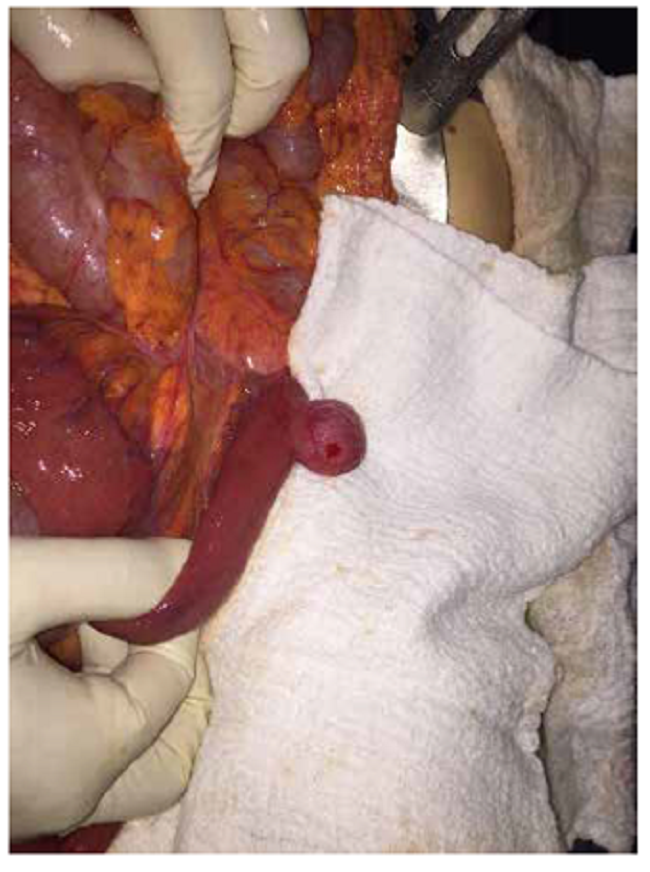

Se hospitalizó para observación y, 48 horas después presentó signos de irritación peritoneal más distensión abdominal importante, por lo que se sometió a laparotomía. En el yeyuno proximal, se encontró una zona de transición por vólvulo del asa intestinal con giro sobre su eje longitudinal, y dilatación proximal y distal de las asas intestinales delgadas. A 10 cm de ángulo de Treitz, se encontró un divertículo en yeyuno, sin serosa, comprometido por el vólvulo e hipoperfusión asociada (figura 3). Con estos hallazgos, se decidió practicar una resección intestinal con anastomosis yeyuno-yeyuno mediante sutura lineal mecánica (figuras 4 y 5).

En el estudio de histopatología se encontró un fragmento de intestino en forma de saco de 2,3 x 1,8 x 1,2 cm, con congestión vascular, sin capa muscular propia, correspondiente a un divertículo adquirido de intestino delgado. Un mes después de la cirugía, la paciente presentaba una evolución clínica adecuada, se encontraba asintomática, recibiendo dieta normal y buen tránsito intestinal yeyuno-yeyuno.